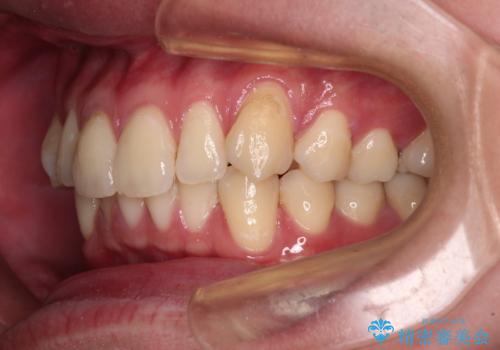

上下のデコボコを治したい インビザラインによる矯正治療

- 前歯のデコボコと突出感を気にして来院された患者様です。

極力目立たない装置を希望とのことで、インビザラインを用いて非抜歯で矯正治療を行うこととしました。

事前に親知らず4本を抜歯し、多少歯列を後方に移動できるように準備をした上で、なるべく歯と歯の間を削ることなくデコボコを解消できるように計画しました。

お仕事が忙しく、1日の装着時間は不十分となる日もありましたが、治療は順調に進めていくことができました。

途中、以前大きなむし歯で処置をした歯が痛み出し、根管治療が必要となったため、根管治療とオールセラミッククラウンによる補綴治療を行い、その後にインビザラインによる仕上げの歯列移動を行い、無事に治療を終えることができました。